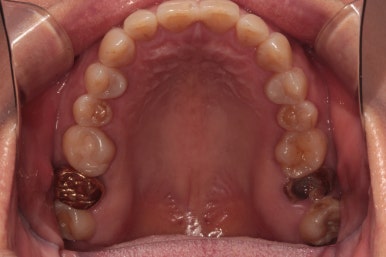

왼쪽: 위턱, 오른쪽: 아래턱

위턱과 아래턱의 교합면 사진입니다.

아래턱 사진을 보시면 치아가 하나 비어있는 것을 아실 수 있죠? 두 개 비어보이시겠지만, 하나는 사랑니니깐 한개로 칩니다. 아까 치과용 파노라마에서 빨간색 동그라미!

위턱 사진을 보시면 뿌리만 있는 치아를 확인하실 수 있을거에요. 노란색 동그라미!

마지막으로 딱 한개 있는 금니를 보실 수 있을텐데, 이차 충치가 있어 다시 치료해야했던 치아입니다. 파란색 동그라미!